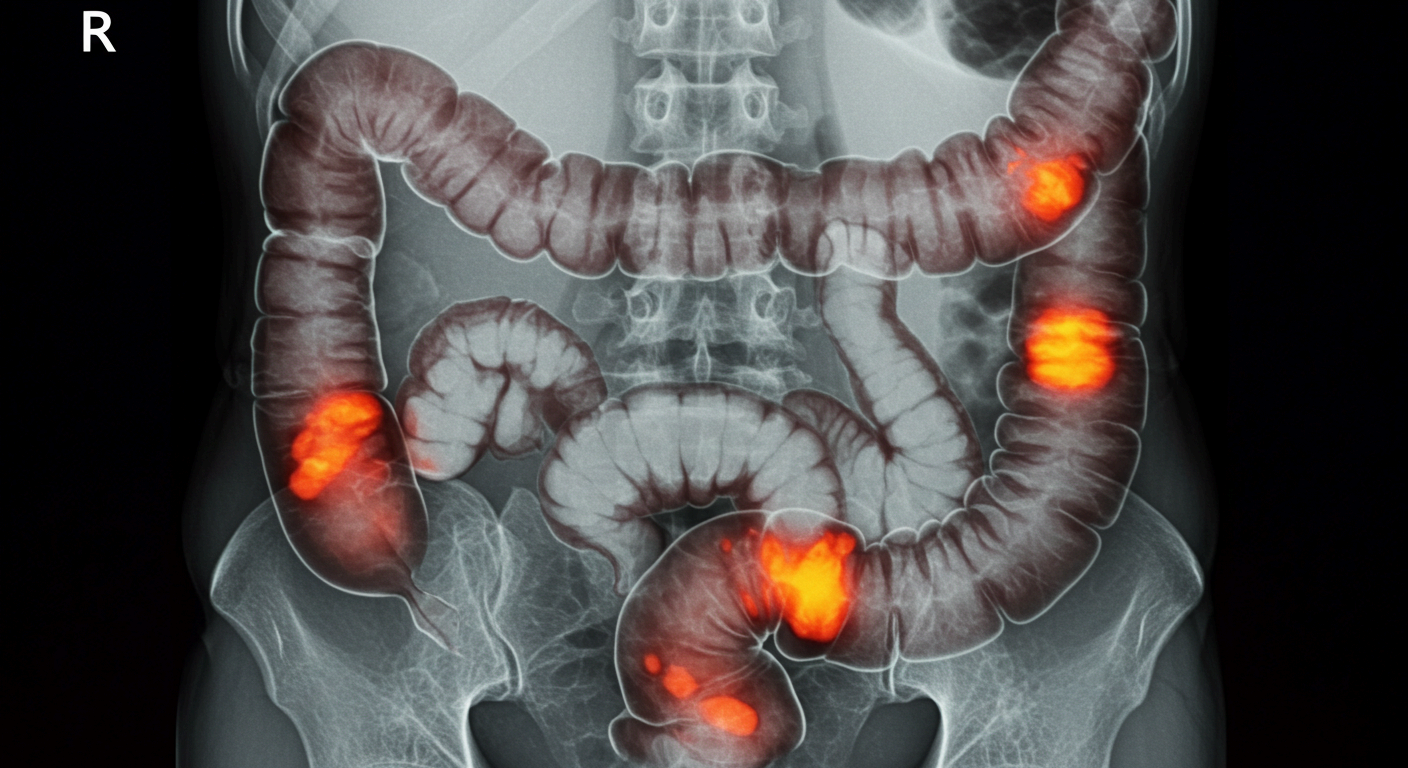

• 종양(암)

특히 대장암은 고령층에서 장폐색의 중요한 원인입니다. 종양이 커지면서 장 내부를 좁히고, 음식물이나 변이 더 이상 내려가지 못하게 막습니다. 소장암, 전이성 암도 원인이 될 수 있습니다.

• 크론병, 장결핵 등 만성 염증성 장질환 환자